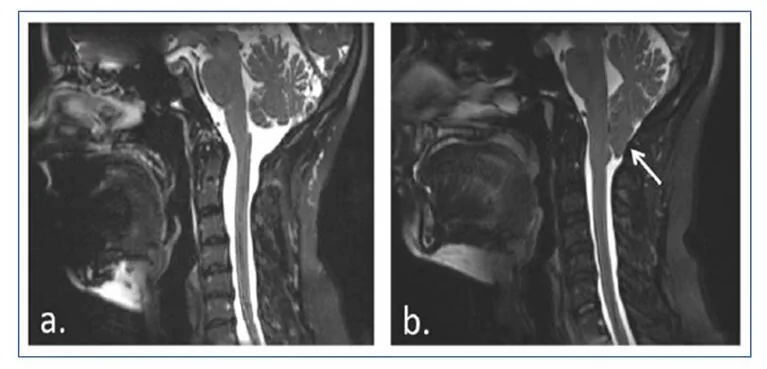

A Malformação de Chiari tipo I implica uma hérniação caudal das amígdalas cerebelosas de aproximadamente 5 mm abaixo do forame magno, que geralmente não vem acompanhada de descenso do tronco encefálico ou do quarto ventrículo nem de hidrocefalia, mas sim de siringomielia.

A siringomielia é causada pela formação de cavidades ou cistos (siringe ou syrinx) cheios de líquido dentro da medula espinhal, que podem expandir-se lentamente, causando um dano progressivo à medula espinhal e hipertensão intracraniana devido à pressão exercida por esse líquido.

Menina diagnosticada com Malformação de Chiari tipo I, com siringomielia, submetida a intervenção cirúrgica aos 12 anos de idade.